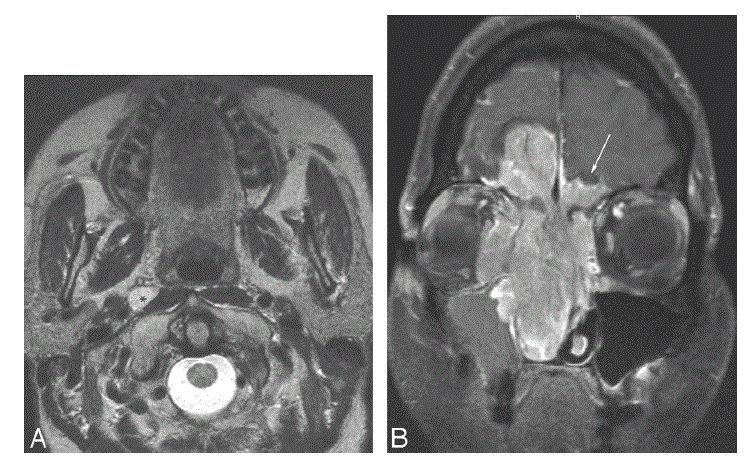

CASO 2. Homem com história de congestão nasal se apresentou em urgência hospitalar com epistaxe. Exames de imagem foram realizados:

Foi identificada uma lesão expansiva que se estendia por cavidade nasal, seios paranasais, base de crânio e apresentava metástase linfonodal.